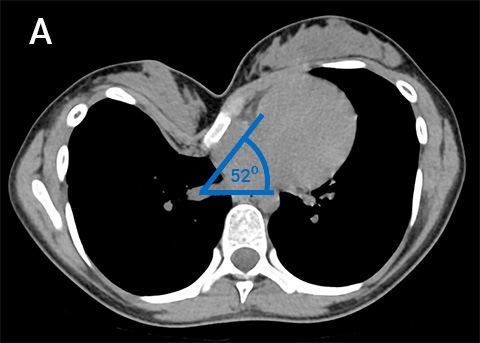

(A) Pre-Operative Chest CT demonstrating severe and asymmetric pectus excavatum with significant sternal rotation. (B) Pre-operative photos before and (C) 2 weeks following Modified Ravitch procedure. (D) Post-operative Chest X-ray showing a 2-bar internal support using a partial ‘cross-bar’ method to maximise correction